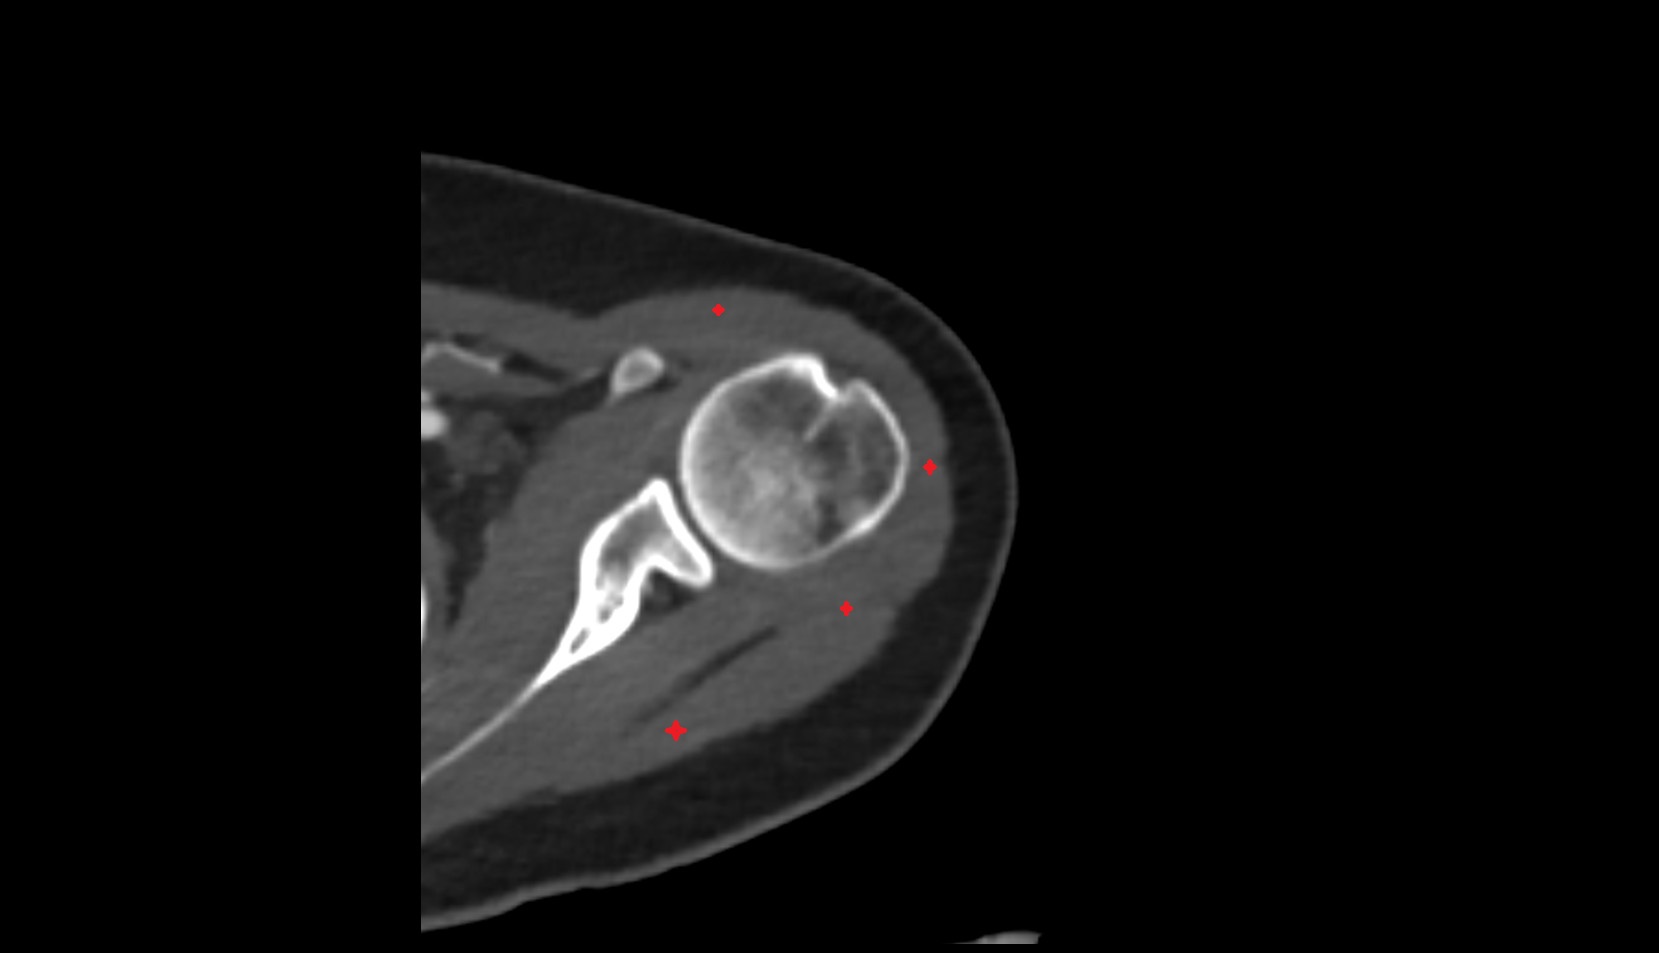

- Glenoid fossa

- Head of humerus

- Shoulder joint (glenohumeral joint)